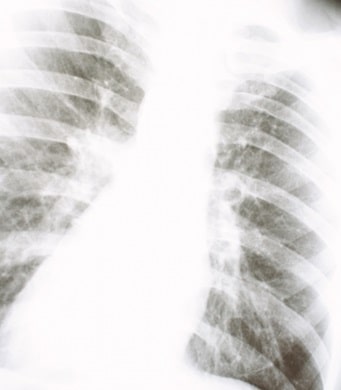

乱心(心の混乱)→ 内的な不均衡 → 慢性ストレス → 癌・難病へと発展する流れ

社会の固定観念によって「今」を見失い、外部依存が強まり、内的な不均衡が続くと、最終的には癌や難病といった深刻な病へと発展する。

この「慢性炎症」が長期的に続くことで、癌や自己免疫疾患(難病)のリスクが大幅に上昇する。

現代社会は、「今この瞬間」を曇らせ、外部基準に従わせることで、慢性ストレス→自律神経の乱れ→慢性炎症→癌・難病 という流れを作り出している。